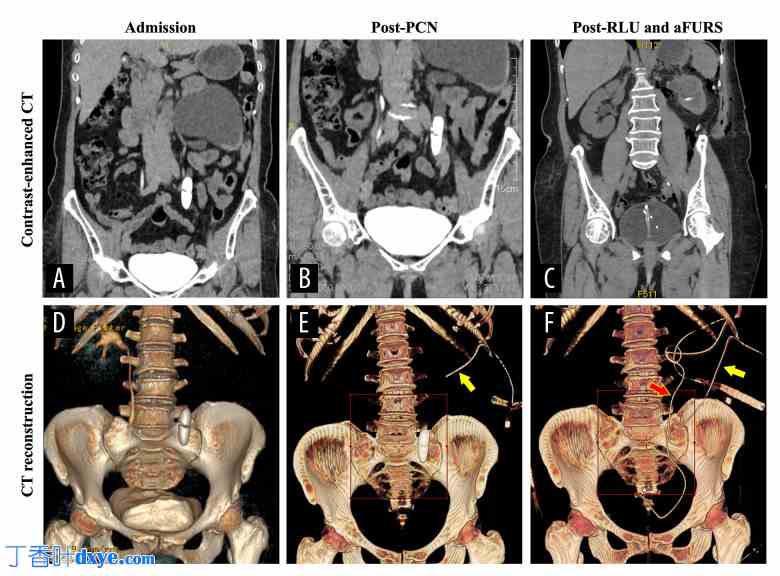

患者增强 CT 扫描图像:(A) 入院时;(B) 经皮肾造瘘术后 1 个月;(C) 经腹膜后腹腔镜输尿管切开取石术及顺行输尿管软镜检查后 5 天。重建 CT 图像:(D) 入院时;(E) 经皮肾造瘘术后 1 个月,可见输尿管(黄色箭头);(F) 经腹膜后腹腔镜输尿管切开取石术及顺行输尿管软镜检查后 5 天,取出肾造瘘管(黄色箭头)并取出完整的输尿管支架(红色箭头)。

紧急行经皮肾穿刺减压术。在超声引导下,经第11肋间隙至肾盏中部进行肾造瘘穿刺,置入14Fr肾造瘘管,引流出70-90 mL深红色液体。患者术后情况稳定,于第3天出院,在家恢复肾功能。

术后47天随访。复查CT扫描显示左侧肾积水改善,右肾发现一处不显著的结石(图1B、1E)。99mTc-DTPA肾动态显像显示左肾灌注显著降低,肾功能分裂百分比为18.02%(右侧为81.98%),肾小球滤过率为10.62 mL/min(右侧为48.30 mL/min;图2)。由于尿道内镜(LU)负担严重,计划择期手术,联合使用RLU和aFURS技术,以完全清除结石。